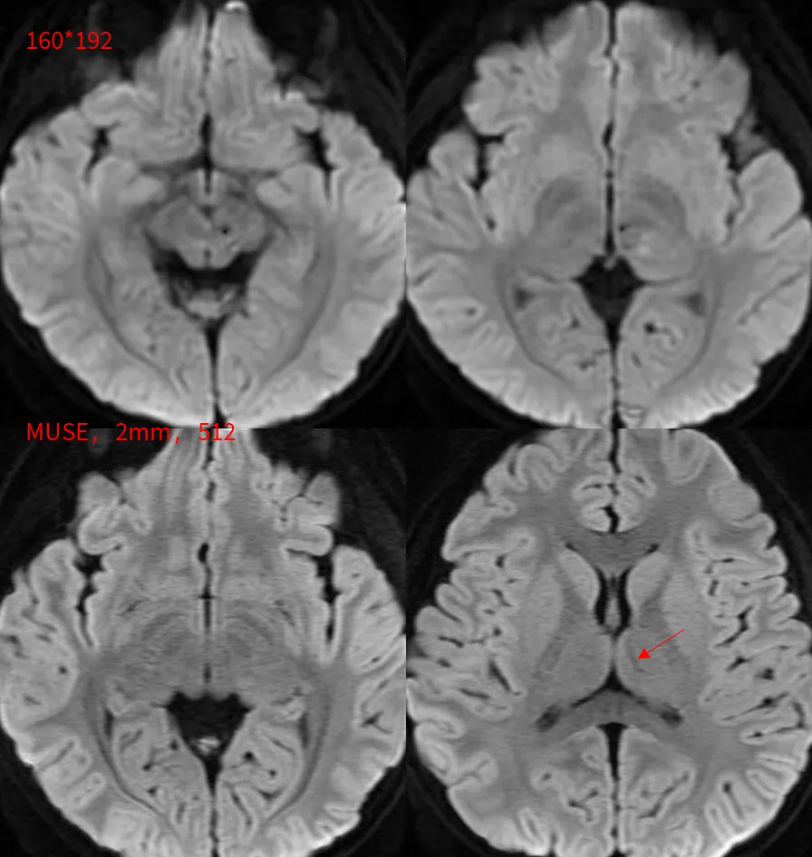

要么再试试薄层DWI: MUSE DWI b1000:FOV = 20 , 160(freq)× 512(phase),2 /0mm。 这根狡猾的小静脉终于露出庐山真面目。

常规DWI层厚5 / 1 mm,160 × 192;分辨率已经挺高的了。但是仍旧会存在严重的容积效应。

这个患儿扫描到MP- RAGE的时候,已经陷入深度睡眠(虽然没有吃药)。所以,我们加扫了SWAN和高清MUSE,2mm,矩阵512。为了降低容积效应,我们已经使出了洪荒之力。